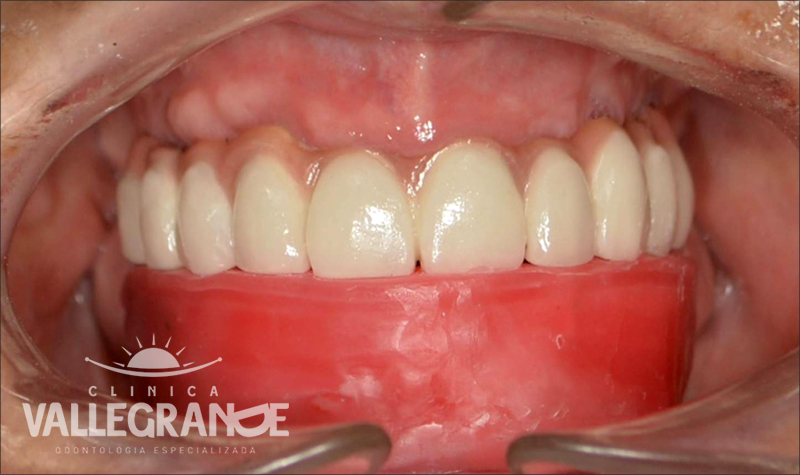

Caso planificado con prótesis híbrida fija completa sobre 4 implantes mandibulares.

Prótesis híbrida inferior de cerámica fija sobre implantes.

Prótesis híbrida superior de cerámica fija sobre implantes.

Prótesis híbrida superior de cerámica fija sobre implantes